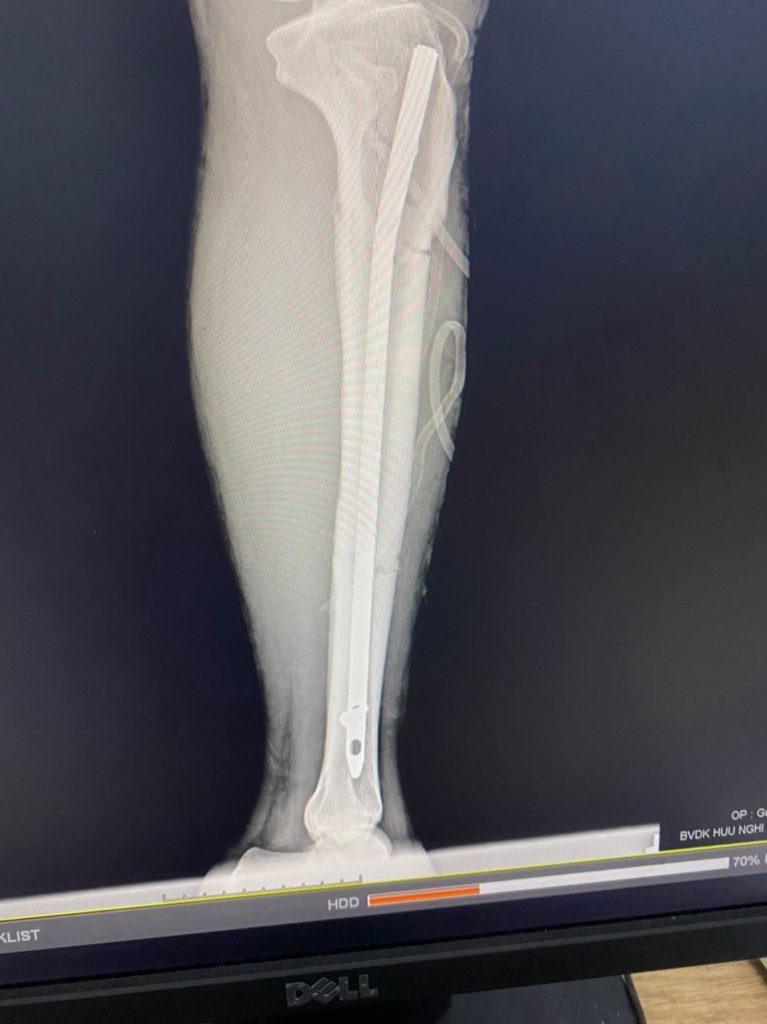

Sau khi hội chẩn chuyên môn, các bác sỹ khoa Ngoại-Gây mê hồi sức đã quyết định tiến hành phẫu thuật bằng phương pháp kết hợp xương bằng đinh Sign cho bệnh nhân. Ca phẫu thuật được thực hiện trực tiếp bởi Bác sĩ CK2 Nguyễn Quang Chung cùng ekip. Chỉ sau hơn một giờ đồng hồ, ca phẫu thuật đã thành công tốt đẹp.

Sau mổ, bệnh nhân được chuyển về Khoa Ngoại-Gây mê hồi sức theo dõi, điều trị và tập phục hồi chức năng. Quá trình hồi phục của người bệnh vô cùng khả quan khi chỉ một ngày sau phẫu thuật, bệnh nhân đã có thể tự tập trên giường và không phải mang bột.